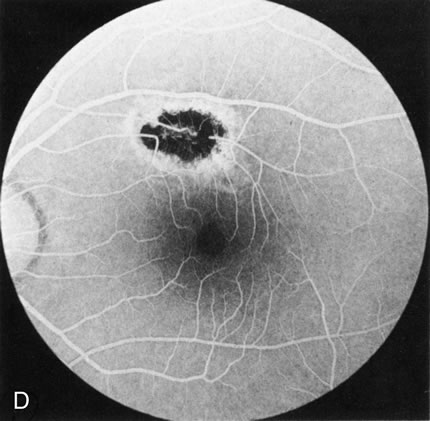

Fig. 6. Generalized choroidal dystrophy. This 65-year-old woman gradually developed enlarging, progressive areas of choroidal atrophy over a 20-year period. When initially seen, the abnormalities were confined to the peripapillary and macular region (A,B). In a recent examination, the generalized choroidal atrophy is vividly demonstrated on angiography (C–F).

Generalized choroidal dystrophy is usually noted in middle-aged mildly symptomatic individuals who show a predominantly peripapillary or pericentral distribution of choroidal atrophy. Gradually, over the years these areas enlarge to eventually involve the entire retina. These changes are vividly seen on FA (Fig. 6).